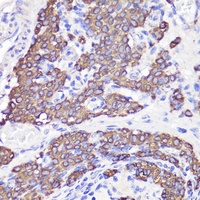

Immunohistochemical analysis of UBL3 staining in rat testis formalin fixed paraffin embedded tissue section. The section was pre-treated using heat mediated antigen retrieval with sodium citrate buffer (pH 6.0). The section was then incubated with the antibody at room temperature and detected using an HRP conjugated compact polymer system. DAB was used as the chromogen. The section was then counterstained with haematoxylin and mounted with DPX.